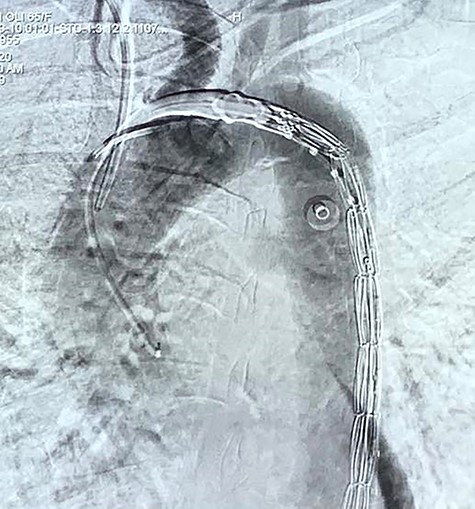

With the above findings, a diagnosis of ruptured descending thoracic aortic aneurysm with AEF was made. The patient was immediately taken for emergency TEVAR where 34 × 34 × 167-mm stent graft (Medtronic Inc. Valiant Thoracic Stent Graft) was deployed using a guidewire beyond the left subclavian artery till above the diaphragm via an incision over the left common femoral artery. Check angiogram showed no leak (Figs 4 and 5). Due to existing mediastinitis, feeding jejunostomy (FJ) was preferred over esophageal stenting. FJ was performed in the same setting after the endovascular procedure.